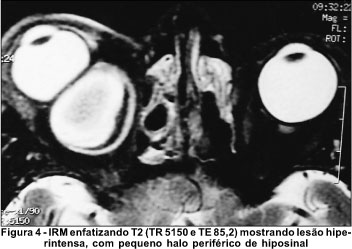

À imagem por ressonância magnética revelou lesão bem delimitada com sinal que nos cortes evidenciando T1 (TR 366 e TE 14) apresentava hiposinal no interior circundado por hipersinal periférico (Figura 3). Nos cortes evidenciando T2 (TR 5150 e TE 85,2) a lesão apresentava-se quase que totalmente hiperintensa, apenas com pequeno halo periférico de hiposinal (Figura 4). Tais achados eram compatíveis com uma lesão contendo sangue recente na periferia e produtos de degradação do sangue (metahemoglobina) indicativos da presença também de sangramento subagudo dentro da lesão.

Esta características são distintas dos achados à IRM obtidos nas outras lesões císticas acima mencionadas, com as quais o cisto hemático faz diagnóstico diferencial. Isto ocorre uma vez que o cisto hemático usualmente apresenta hemorragias em diferentes fases, uma vez que é comum o resangramento dentro da lesão. Hemorragias agudas demonstram sinal intermediário em T1 e muito diminuído em T2, como pode ser observado na periferia da lesão em nosso paciente (Figuras 3 e 4). Hemorragias na fase subaguda mostram hipersinal periférico tanto em T1 como em T2 devido ao acúmulo periférico de metahemoglobina (Figuras 3 e 4). Na fase crônica, todo o hematoma mostra sinal de alta intensidade(9-10). Nosso paciente apresentava, portanto, hematoma com características agudas (na periferia) e subagudas (na sua maior parte). Tais achados são muito distintos de outras lesões tumorais acima mencionadas, incluindo o cisto hidático da órbita, que geralmente mostram sinal baixo em T1 e alto em T2 e com as quais o cisto hemático faz diagnóstico diferencial(9,11).